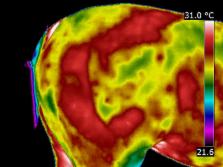

Equine Thermography will help you track changes over time; both prior to, during and post treatment. It provides a great tool in the recovery process, providing the veterinarian, farrier, therapy specialist or owner with a visual aid for monitoring the effectiveness of treatment and allowing changes to be made as the case progresses.

First I take an Initial Full Scan. This will show not only the extent of the known injury but also how the injury has impacted on the horses body as a whole. I then take periodic scans of the injury site to track the healing process.